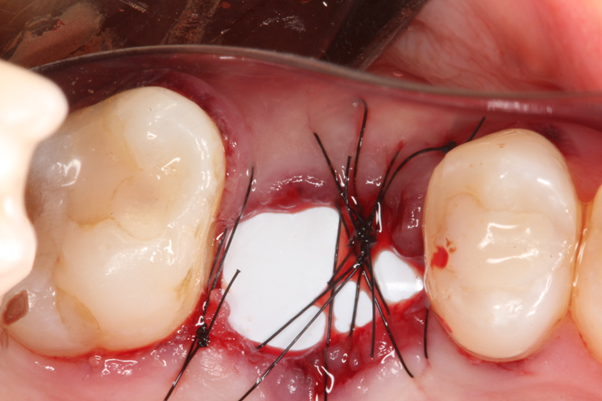

Paciente C.B.F.J., 33 anos, leucoderma, não-fumante e em boas condições de saúde sistêmica, relatou sensibilidade dolorosa durante mastigação no elemento 26, que já possuía tratamento endodôntico, pinos metálicos intrarradiculares e coroa metalocerâmica (Figura 1). Foi solicitada tomografia computadorizada de feixe cônico, na qual a imagem sugeriu fratura radicular na região da furca, descontinuidade óssea da cortical de seio maxilar e opacificação parcial do seio maxilar esquerdo (Figura 2). Foi realizada a exodontia e pôde-se confirmar a comunicação oroantral (Figura 3). Após curetagem do alvéolo, sem preocupação em curetar e remover a lesão cística sinusal, uma barreira reabsorvível foi recortada e posicionada no fundo do alvéolo para obliterar a descontinuidade óssea e impedir que células de tecido mole oriundas da cavidade sinusal invadissem a região alveolar (Figura 4). O alvéolo foi preenchido totalmente por coágulo sanguíneo do paciente (Figura 5) e o alvéolo foi selado por uma barreira não-reabsorvível (Figura 6), impedindo a invasão de fibroblastos do tecido gengival para dentro do alvéolo. Após duas semanas, a barreira estava estável e, então, foi removida, desnudando um tecido de granulação osteoblastogênico (Figura 7).